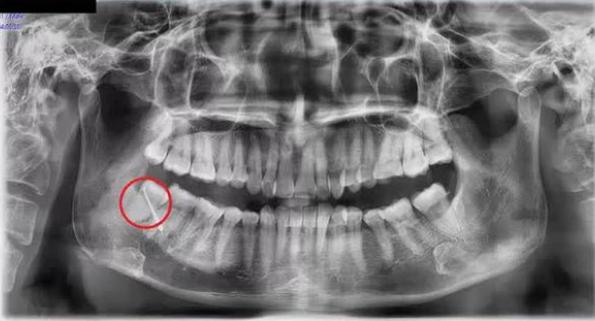

Các bác sĩ chỉ định nhập viện điều trị ngay với chẩn đoán: Áp xe vùng má phải do răng số 48 mọc lệch. Đồng thời, thực hiện phẫu thuật cắt đường dò má và nhổ răng nguyên nhân. Đây là chiếc răng khôn nằm tại vị trí hàm dưới bên phải trên cung hàm của bệnh nhân.